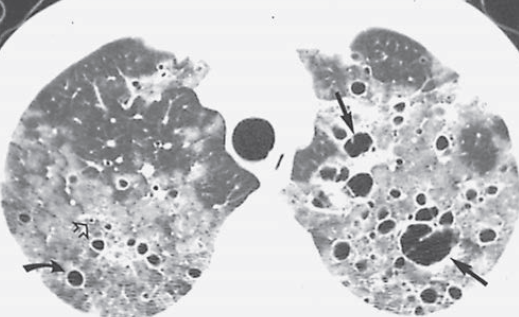

CT

- Pneumatocèles = Kystes septés, à paroi épaisse (Risque de pneu)

Pneumatocèles = Kystes septés, à paroi épaisse

Pneumatocèles = Kystes septés, à paroi épaisse